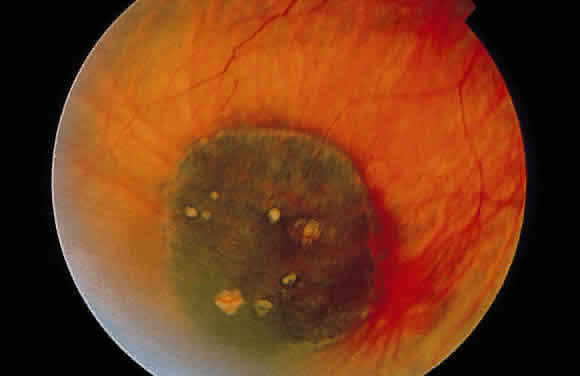

Congenital hypertrophy of the RPE occurs as a flat, round, usually hyperpigmented fundus lesion (Fig. 17). Often, a thin hypopigmented ring comprises the border of the abnormality. In contrast to inflammatory diseases, which produce RPE hyperplasia with rough edges, the margins of congenital hypertrophy of the RPE are well delineated (Fig. 18A). Commonly, depigmented lacunae can be seen within the confines of the lesion (see Fig. 17).

Fig. 17. Congenital hypertrophy of the retinal pigment epithelium. The flat lesion is essentially black with interspersed yellow-orange areas (lacunae) and has a well-circumscribed border. (Courtesy of Dr. Jerry Shields)

Histologically, congenital hypertrophy of the RPE is characterized by a monolayer of large RPE cells containing larger-than-normal pigment granules (Fig. 19; see Fig. 18B through E). Overlying photoreceptor elements have been shown to be degenerated, which explains the localized visual field defects corresponding to these areas.170